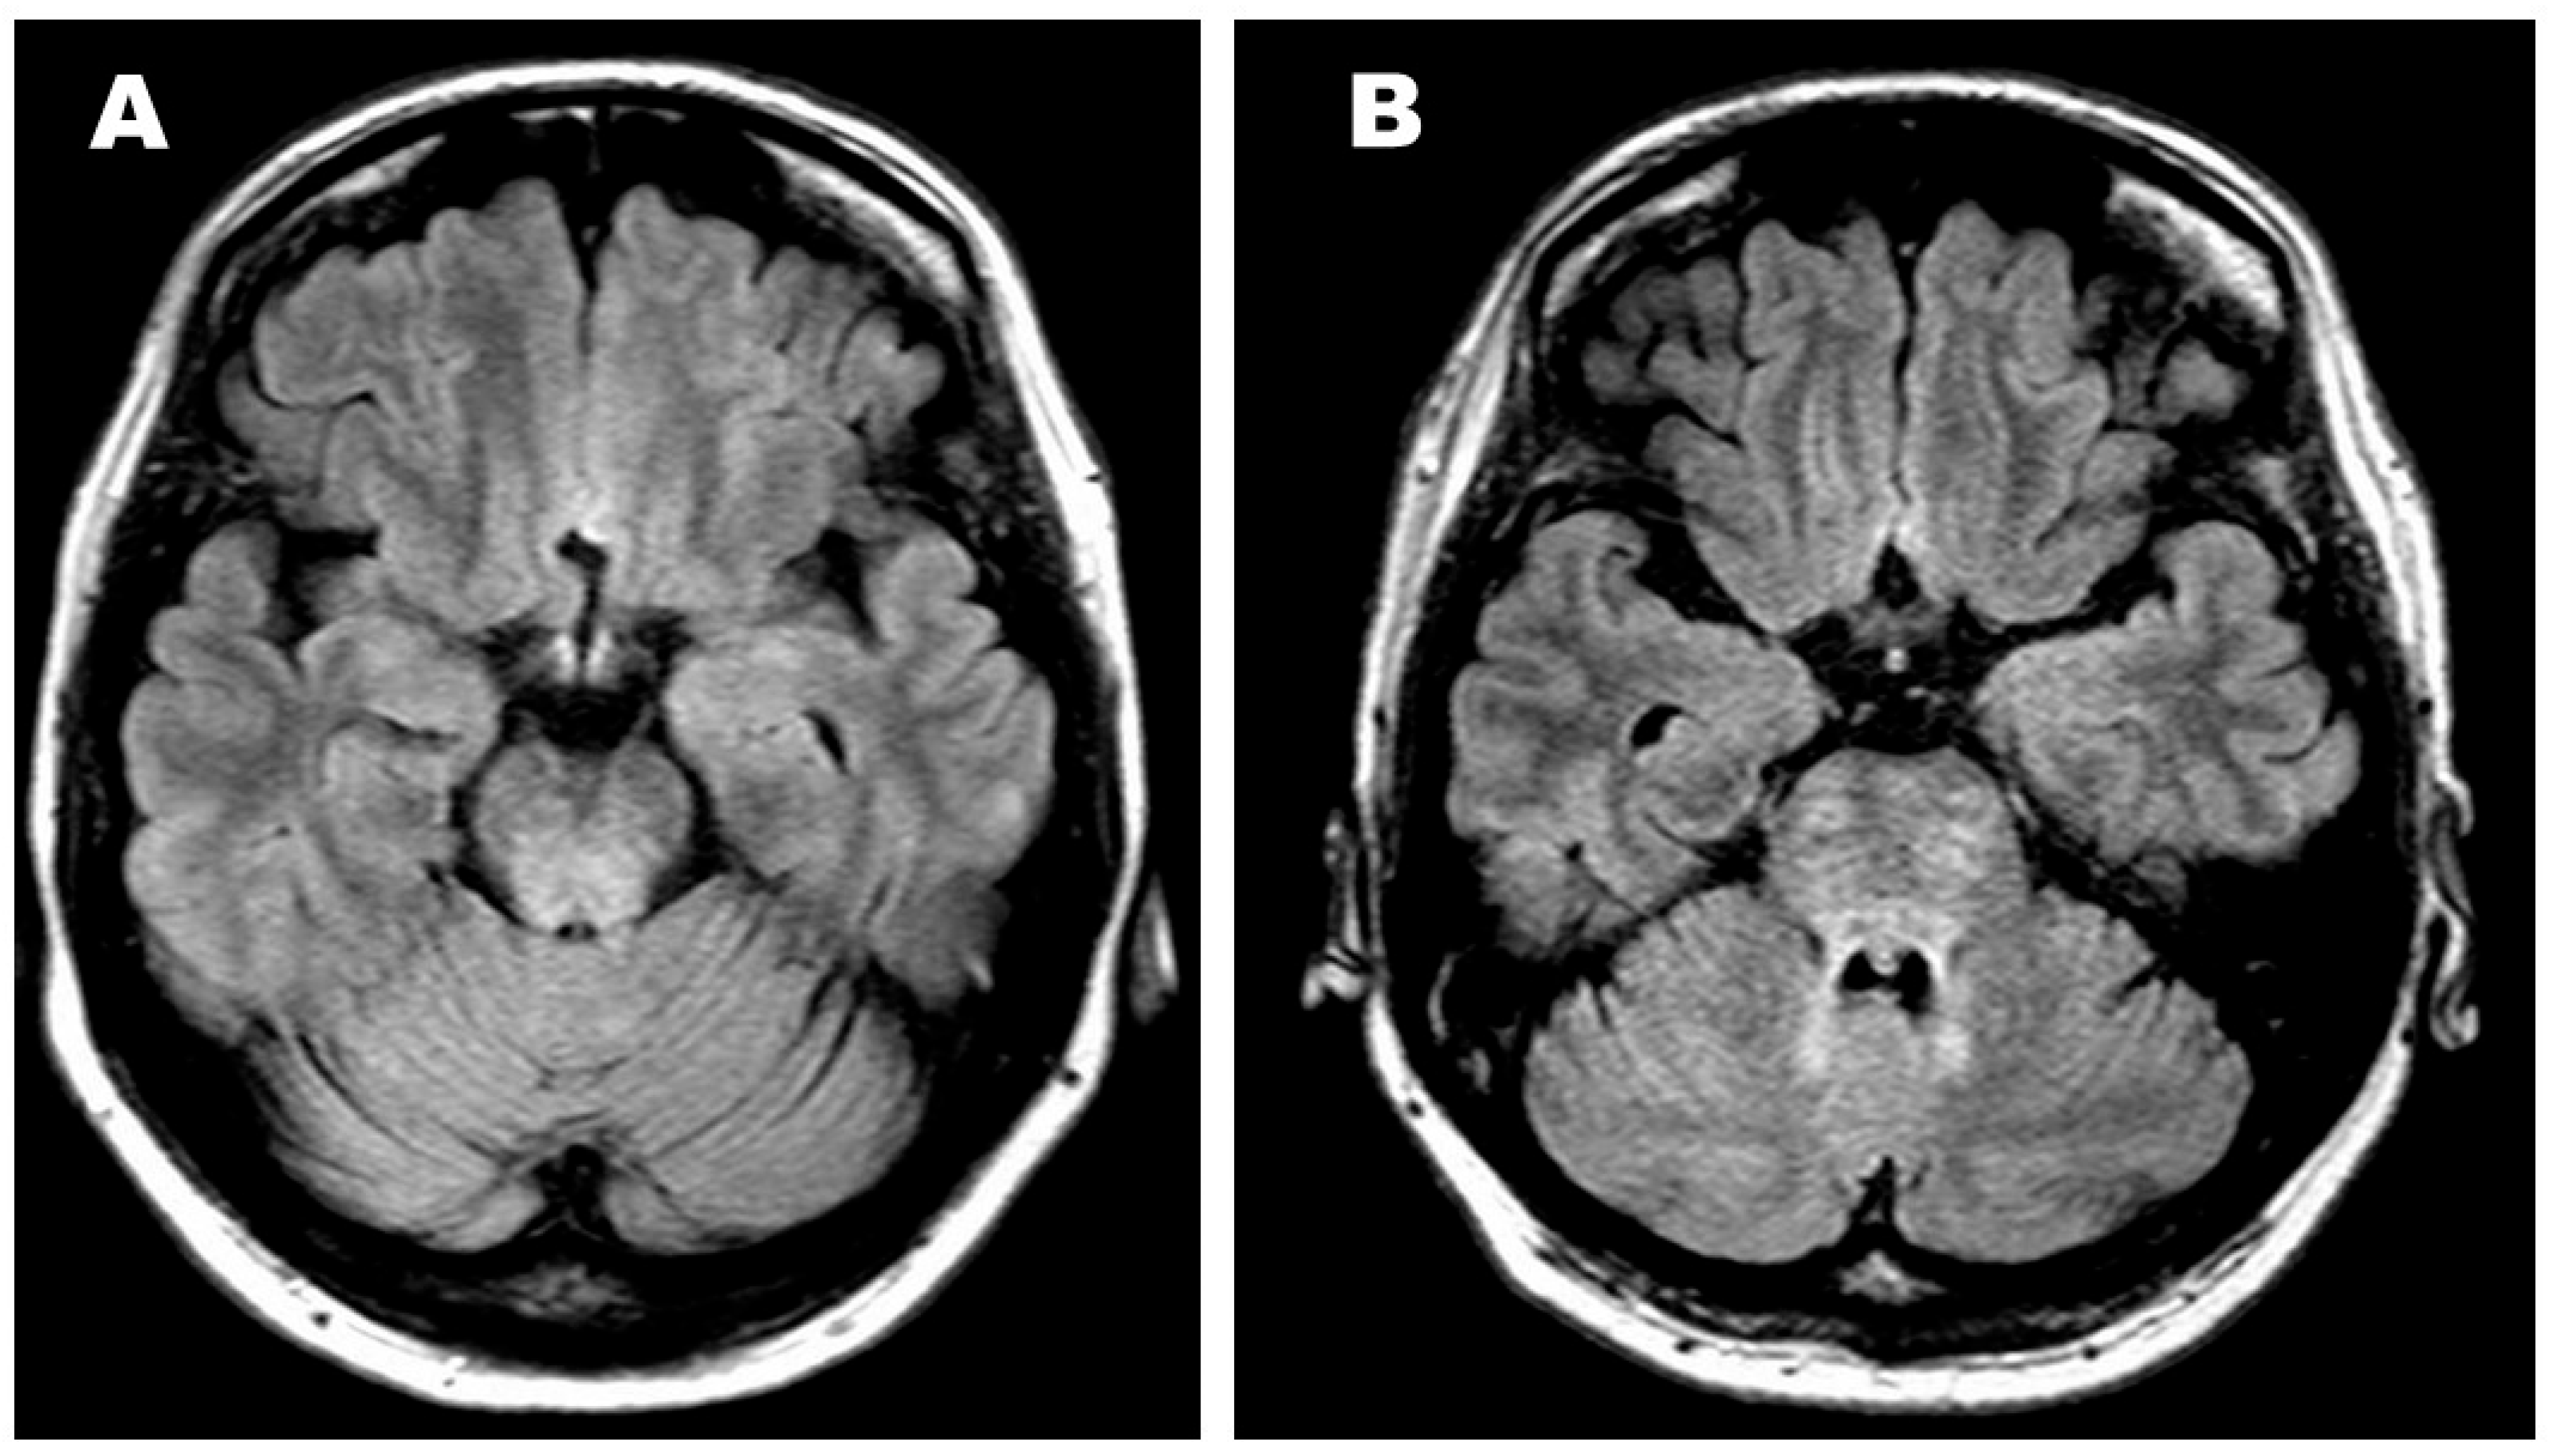

2.2. Evaluation of Targeted Treatment

2.3. Outcome of Targeted Treatment